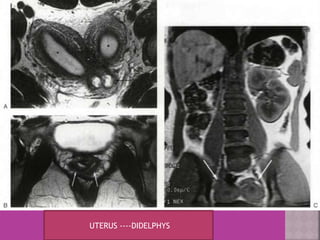

UTERUS ----DIDELPHYS

 Congenital uterovaginal anomalies—

bicornuate, septate,subseptate ,

unicornuate, didelphys ,rudimentary horn

and vaginal atrasia etc

 MRI Is more accurate and informative in diagnosis of

congenital malformation of genito-urinary tract.